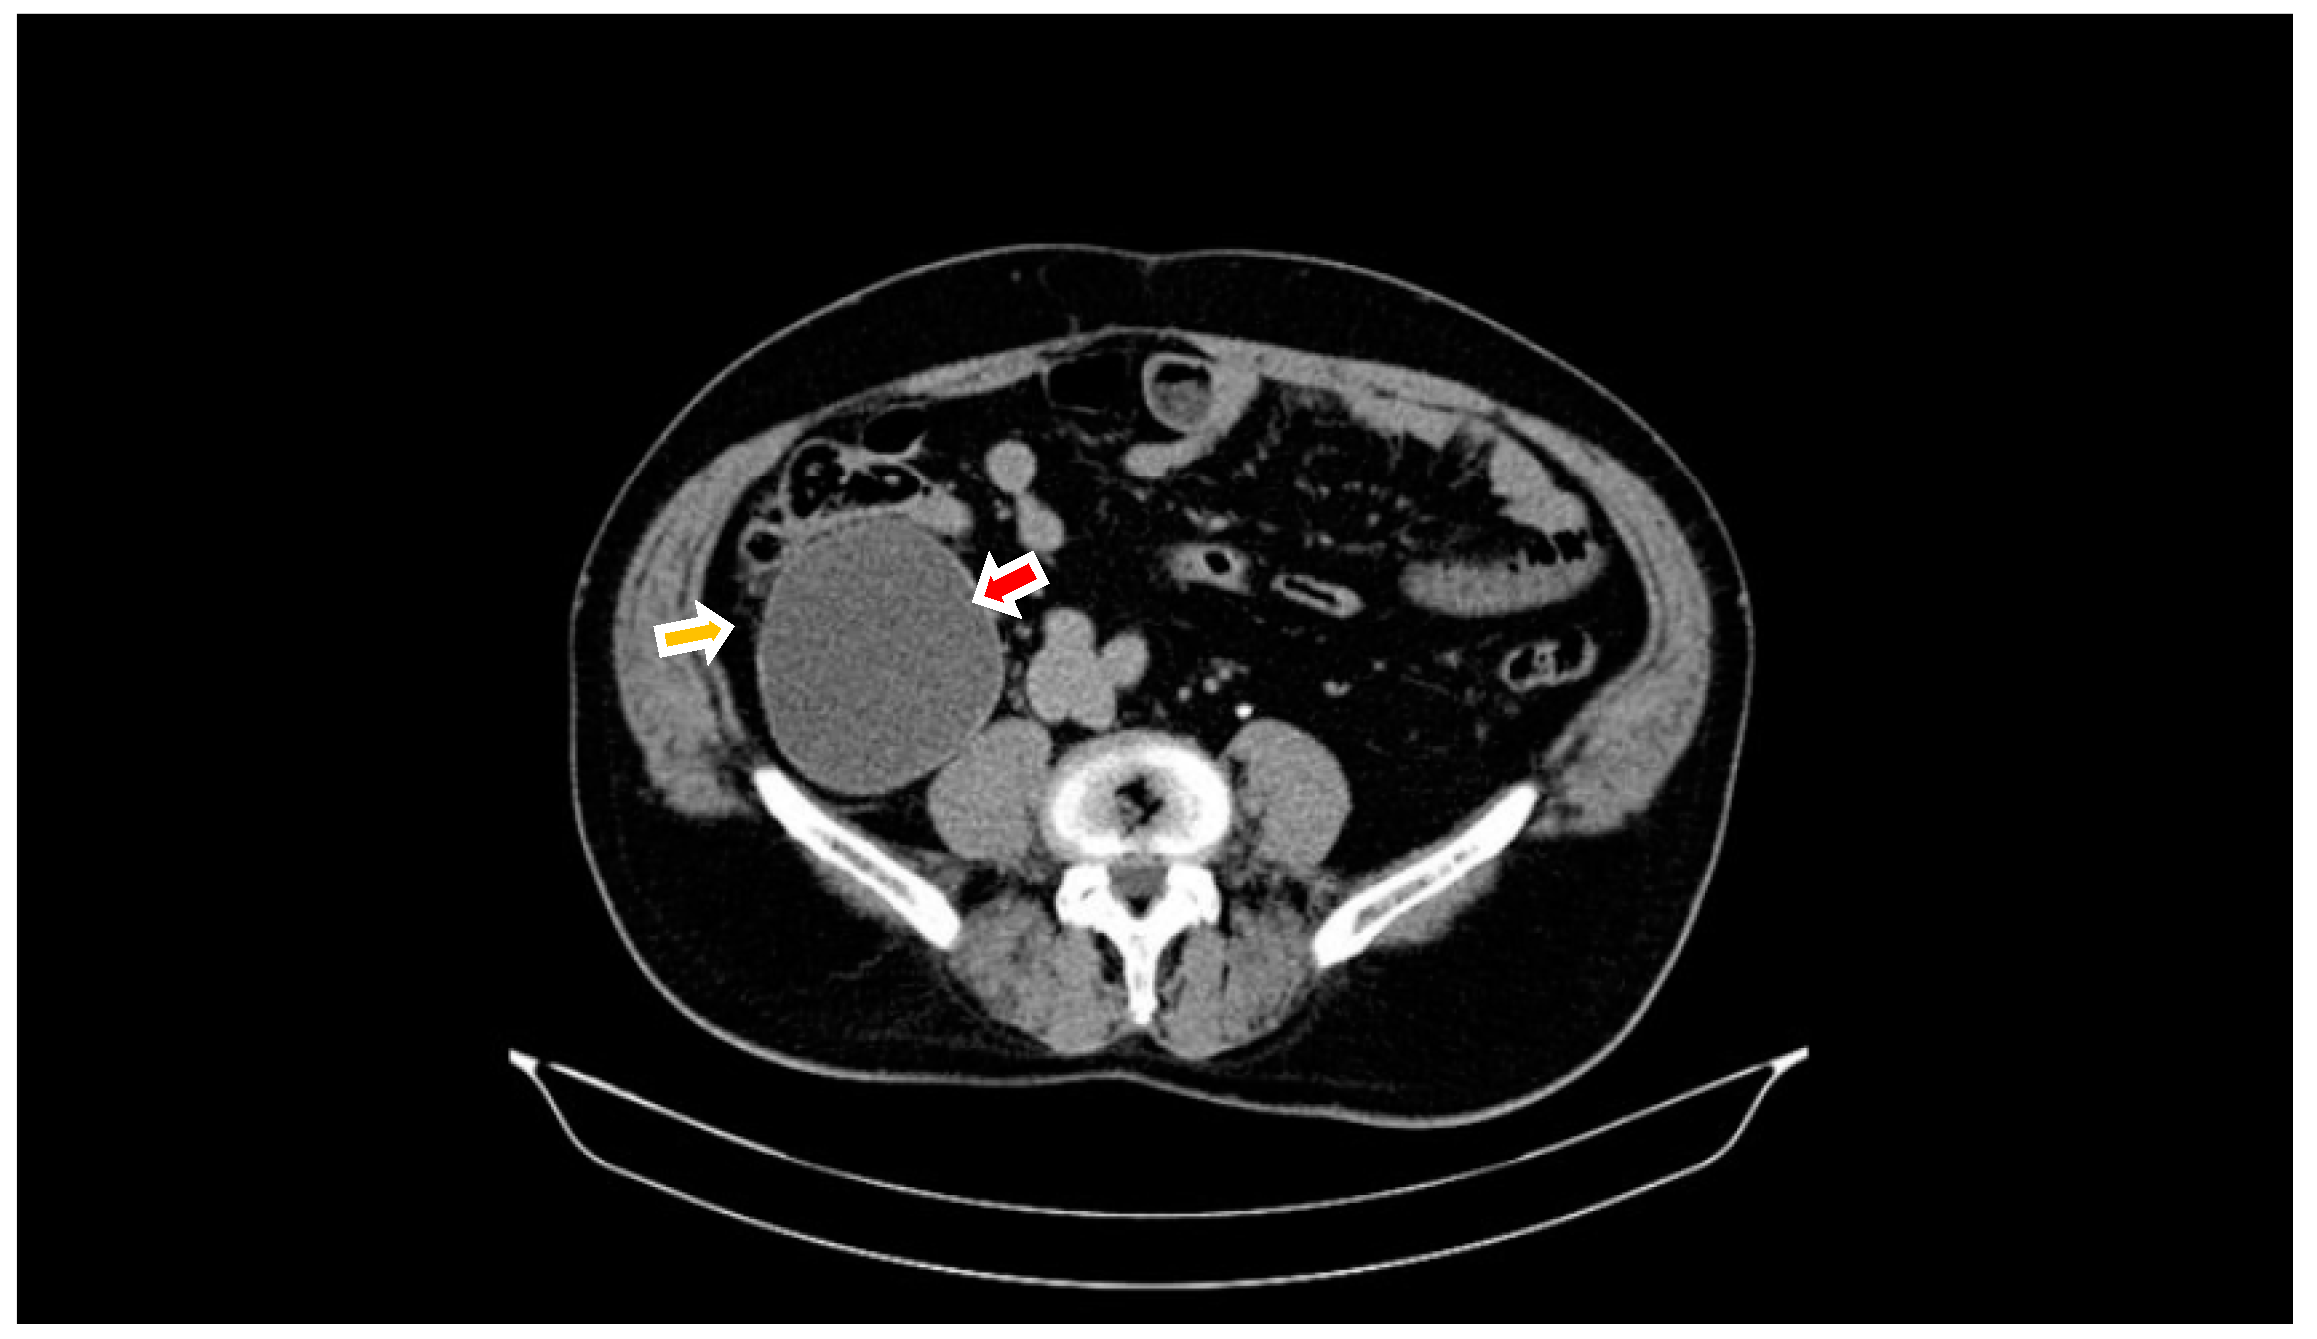

2. Case Report